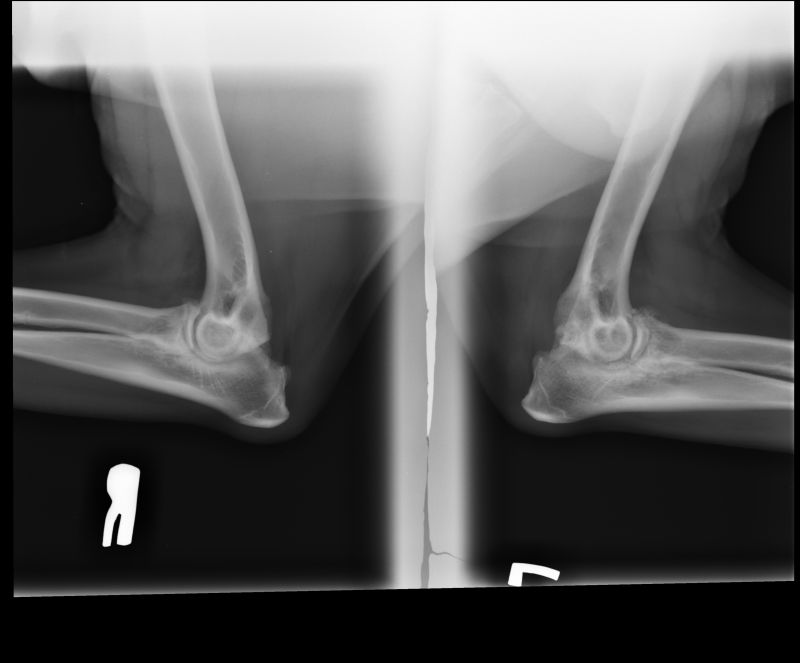

Abnormal Pathology on your pet

Shown on x-ray images which we have taken over the years.

Some interesting patient cases